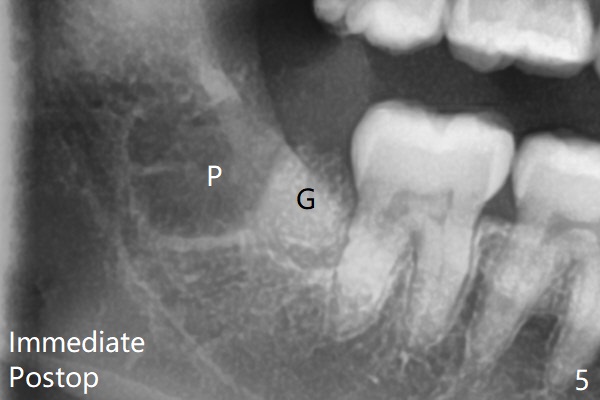

Therefore bone graft seems to be able to be packed mesially (Fig.5: G).  In fact the left Inferior Alveolar Canal is exposed after extraction, collagen plug (P) is placed distal without use of curette around the exposed canal.   Bone graft is highly necessary with patients age>25 with bony defects distobuccal to 2nd molars.